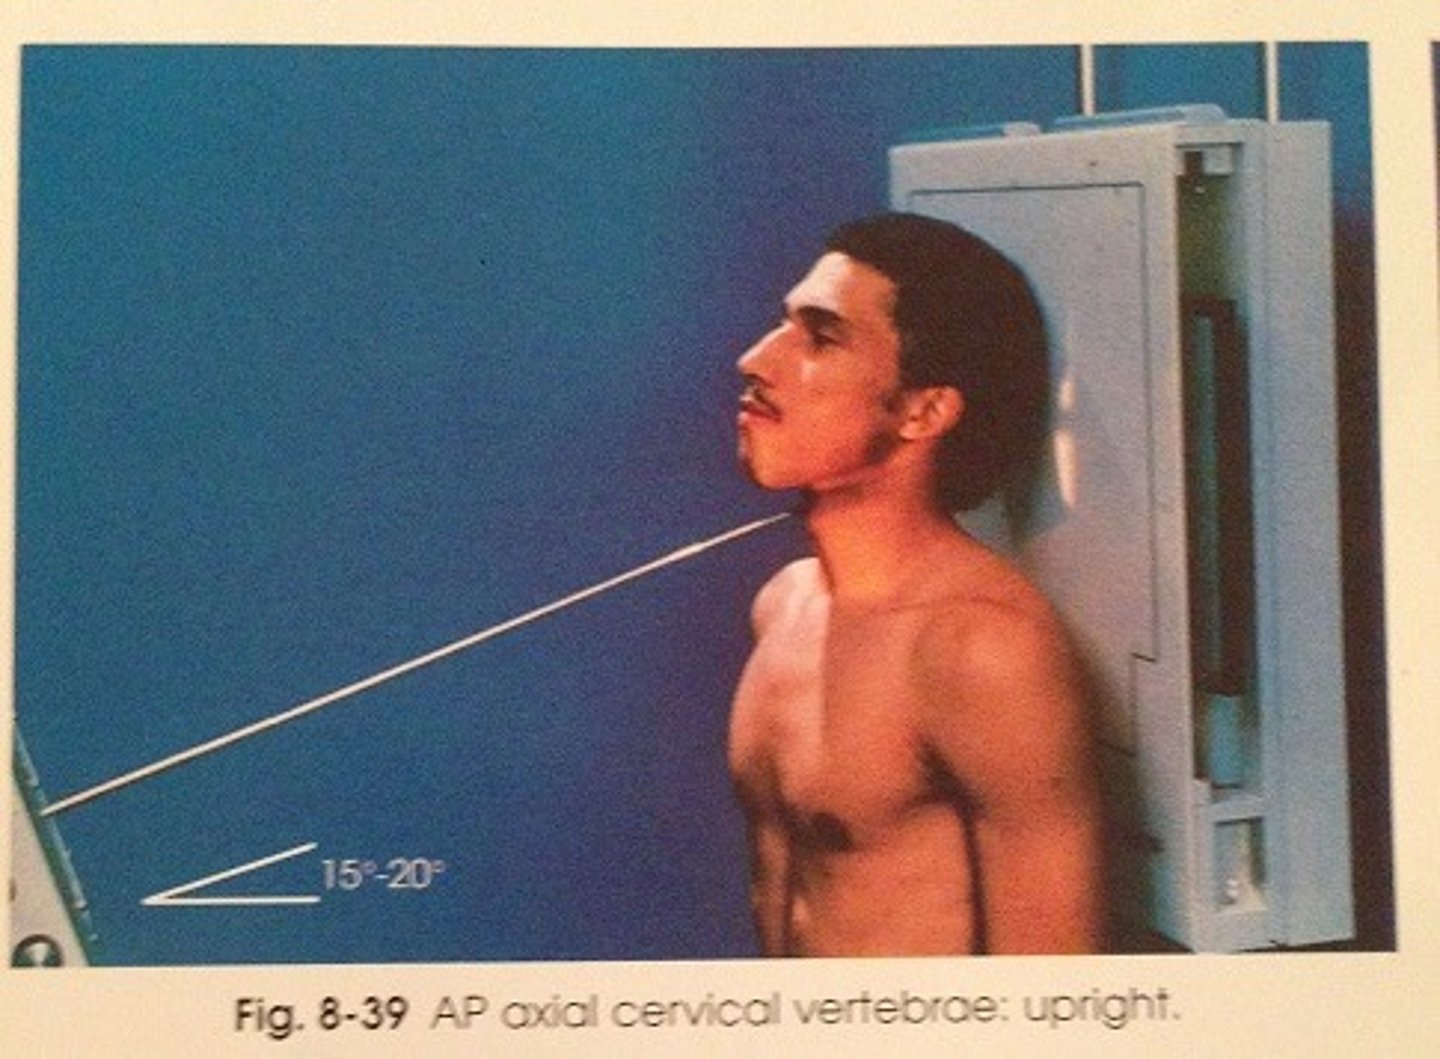

Go through the STAMPSBC list for the AP Axial C-spine

S - shielding around waist

T - 18 mAs @ 75 kVp

A - 15 degree cephalad

M - marker along curve of neck

P - back against board, chin elevated slightly

S - 40

B - suspend breathing

C - 10 x 12 lengthwise, can collimate to 8 x 10

Where do you center for the AP Axial C-spine?

C4 - C5